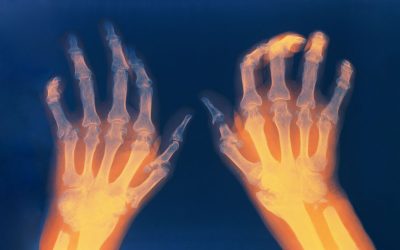

Vitamina D e Doenças Autoimunes Reumatológicas

A vitamina D tem vindo a revelar um papel cada vez mais relevante como imunomodelador, despertando grande interesse nas doenças autoimunes e imunomediadas.